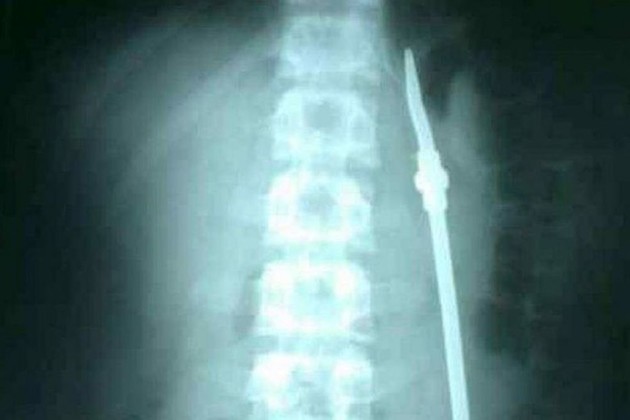

Luego de algunos estudios, los médicos detectaron que el joven efectivamente se había tragado una bombilla, pero fue intervenido quince días después. Cuando finalizó la operación, el detenido aprovechó un descuido de la custodia y se fugó.